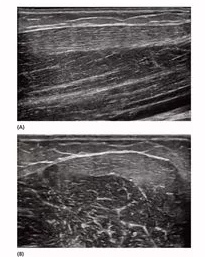

正常的肌肉、肌腱及韧带都有均匀的纹理和自然的走形。肌肉、肌腱断裂时,超声可显示局部纹理的连续性中断;水肿和炎症则可以导致局部组织的回声减低或增高及纹理的改变。